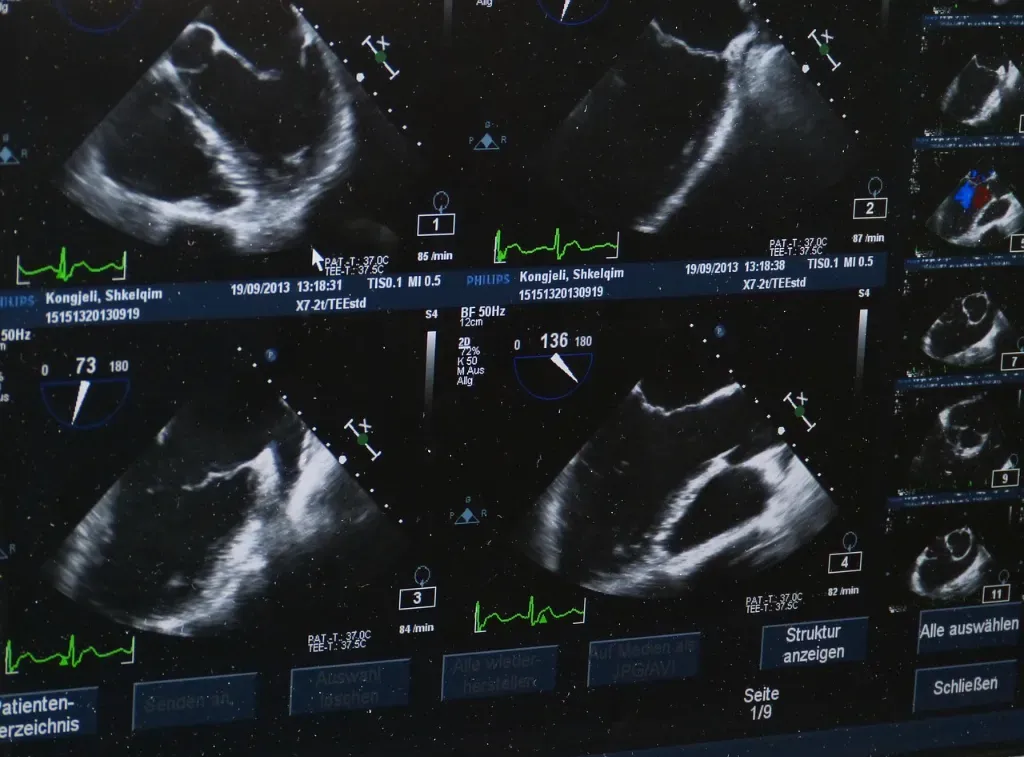

Badanie USG wykorzystuje fale ultradźwiękowe odbijające się od tkanek. Aparat zamienia je na obraz oglądany na żywo. Dzięki temu można ocenić położenie, kształt i ruch struktur wewnętrznych, a w badaniach dopplerowskich również przepływ krwi w naczyniach. To metoda nieinwazyjna i uważana za bezpieczną, dlatego bywa stosowana zarówno u dorosłych, jak i u kobiet w ciąży, kiedy istnieją ku temu wskazania medyczne.